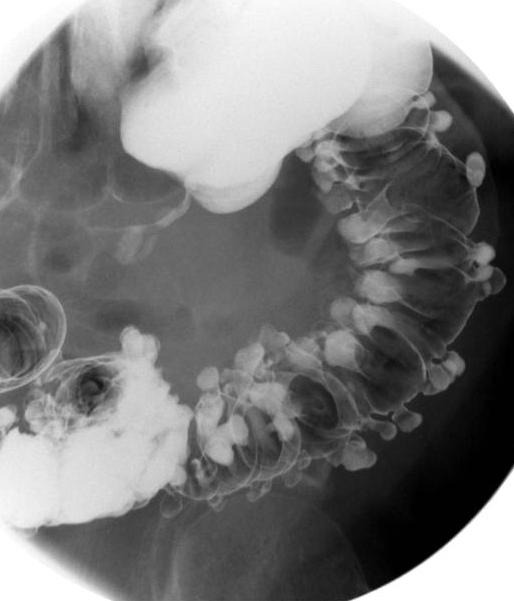

- Image

radiologique de diverticule du colon descendant et

une partie du colon transverse . Les diverticule en

face se donne une image resemble des polyps, ce

qu'il peut elimine par la reste de baryte dans le

sac de diverticule . Lavement baryte en double de

contrast . |